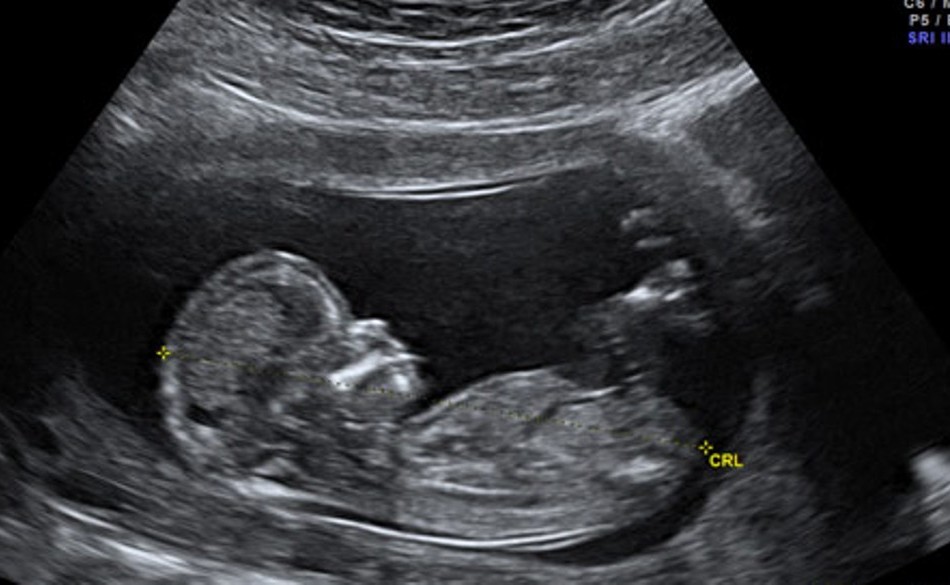

Con người được hình thành từ khi nào?